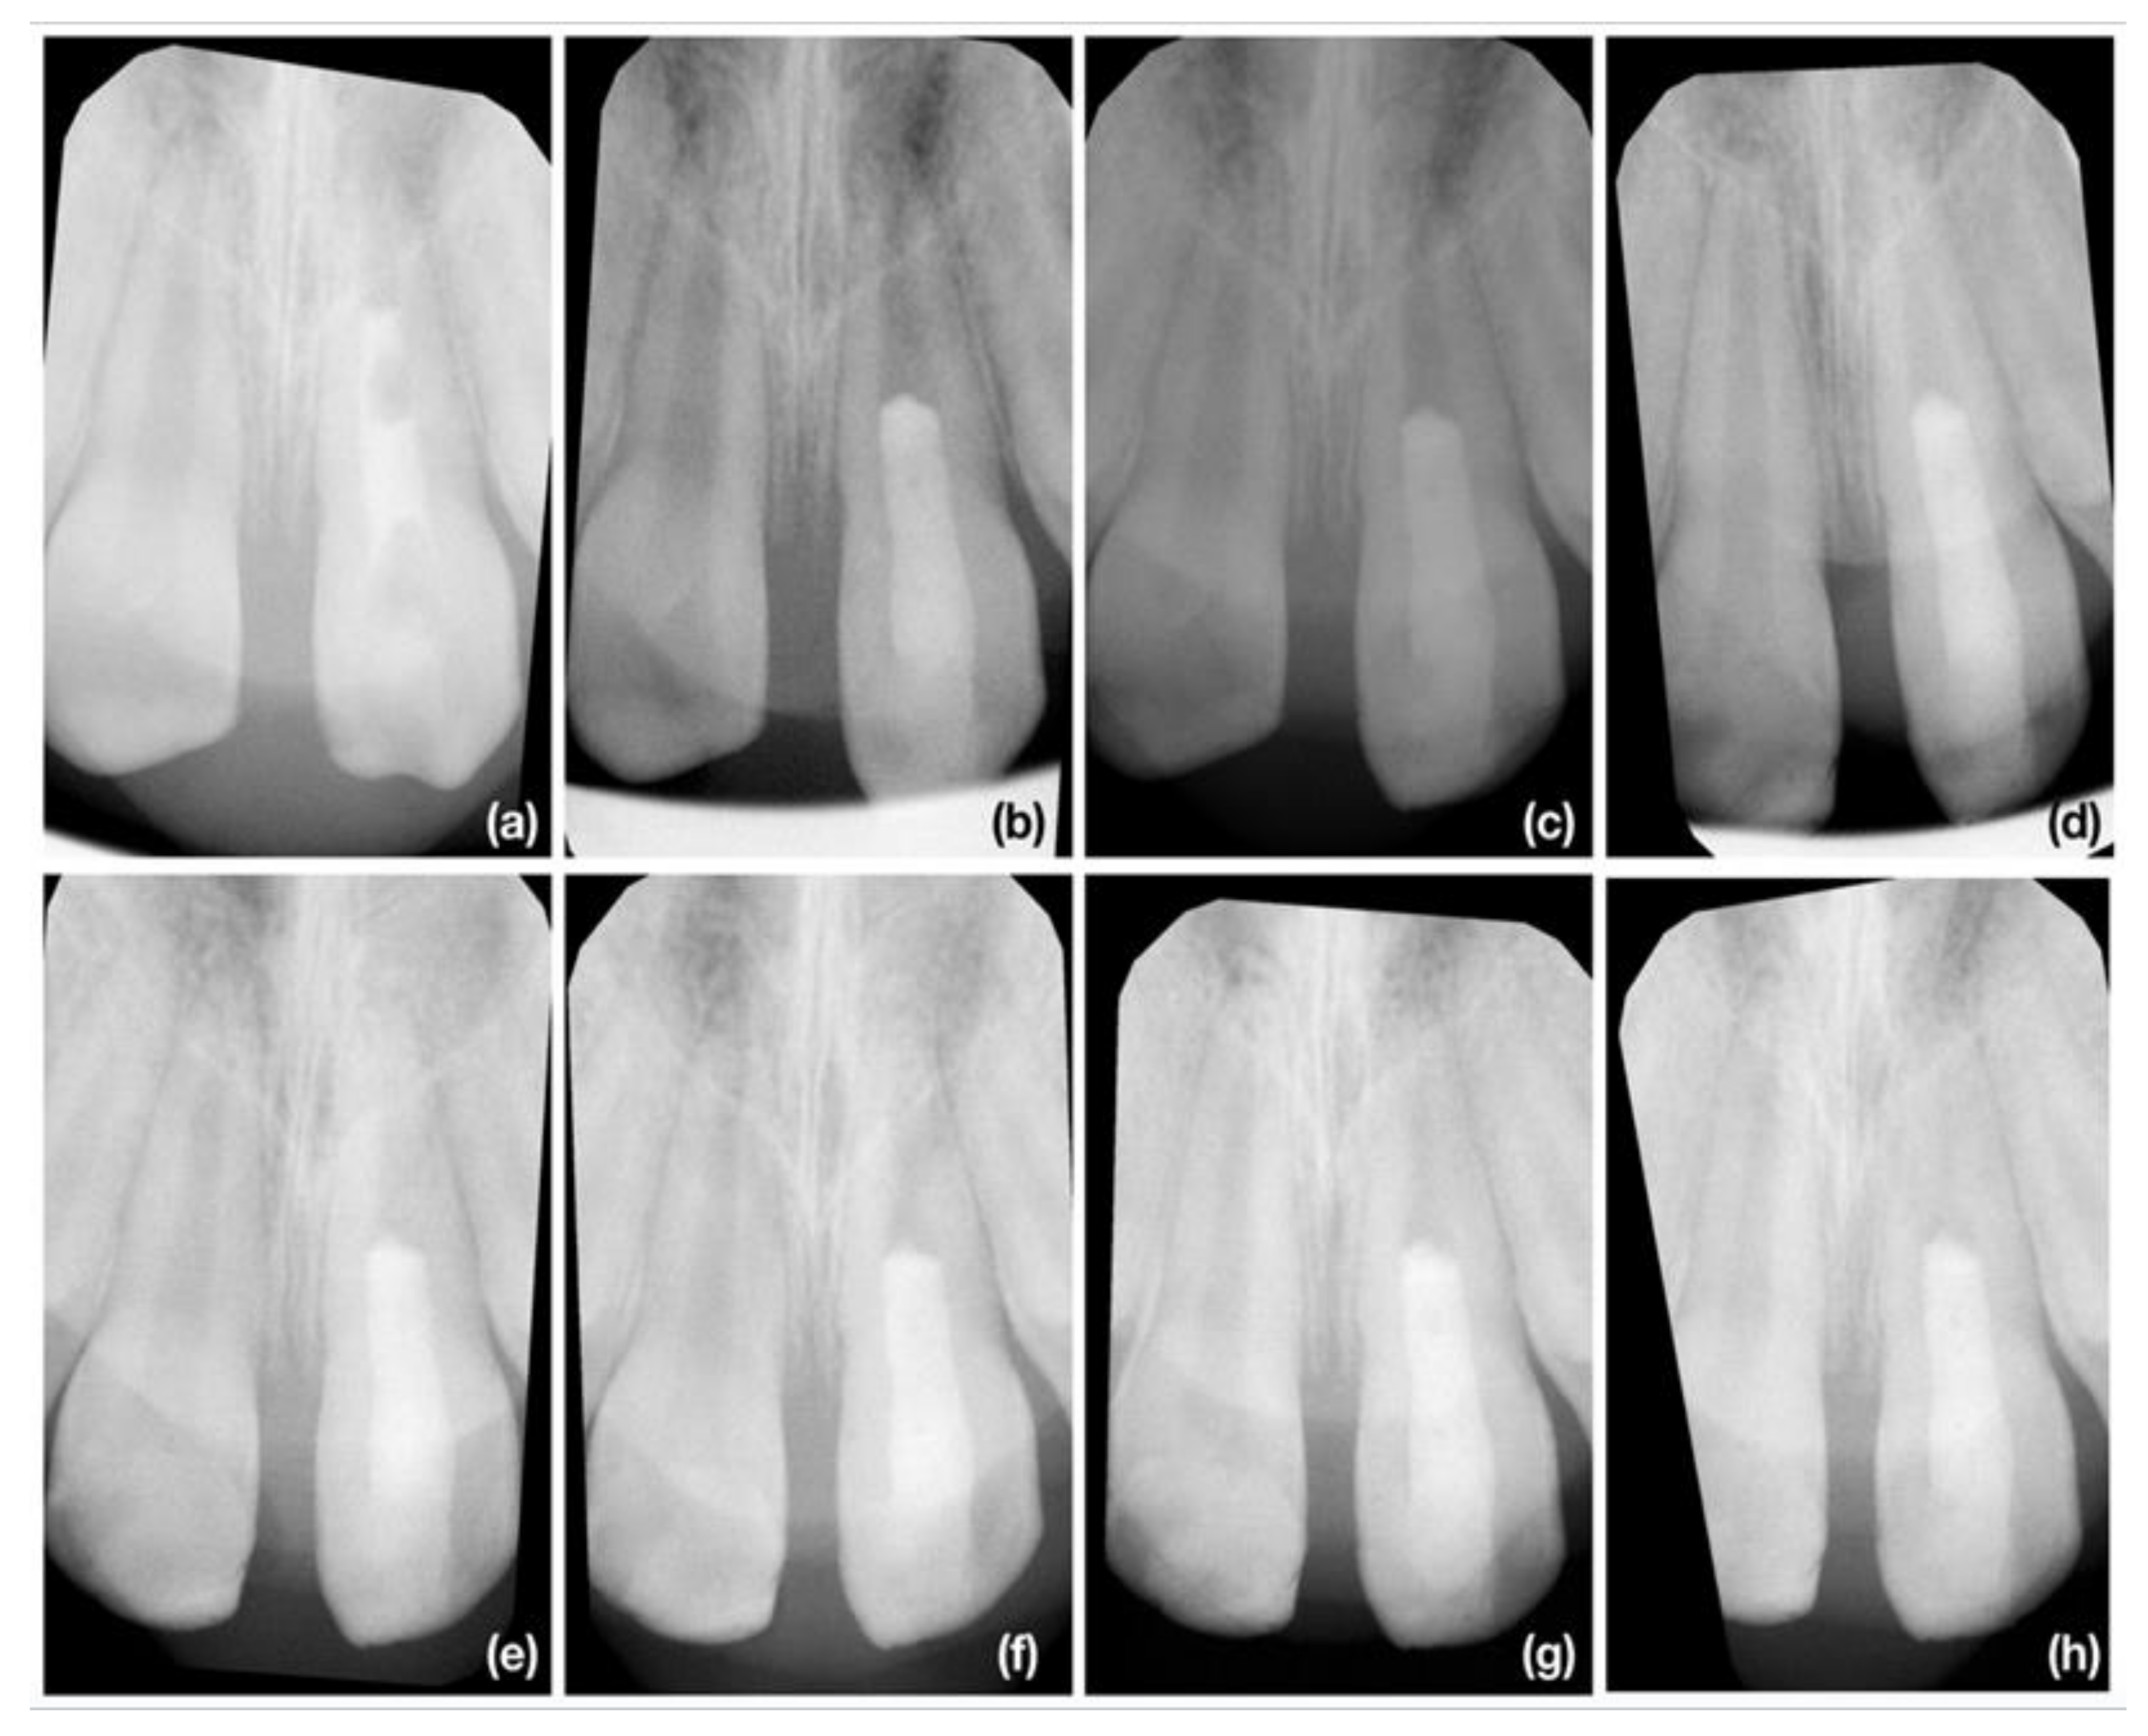

2.4. Radiographic Assesment

2.4.2. Radiographic Root Length Measurement

2.4.3. Radiographic Root Width Measurement

2.4.4. Radiographic Root Area Measurement

3.2. Radiographic Root Length Change

3.3. Radiographic Root Width Change

3.4. Radiographic Root Area Change